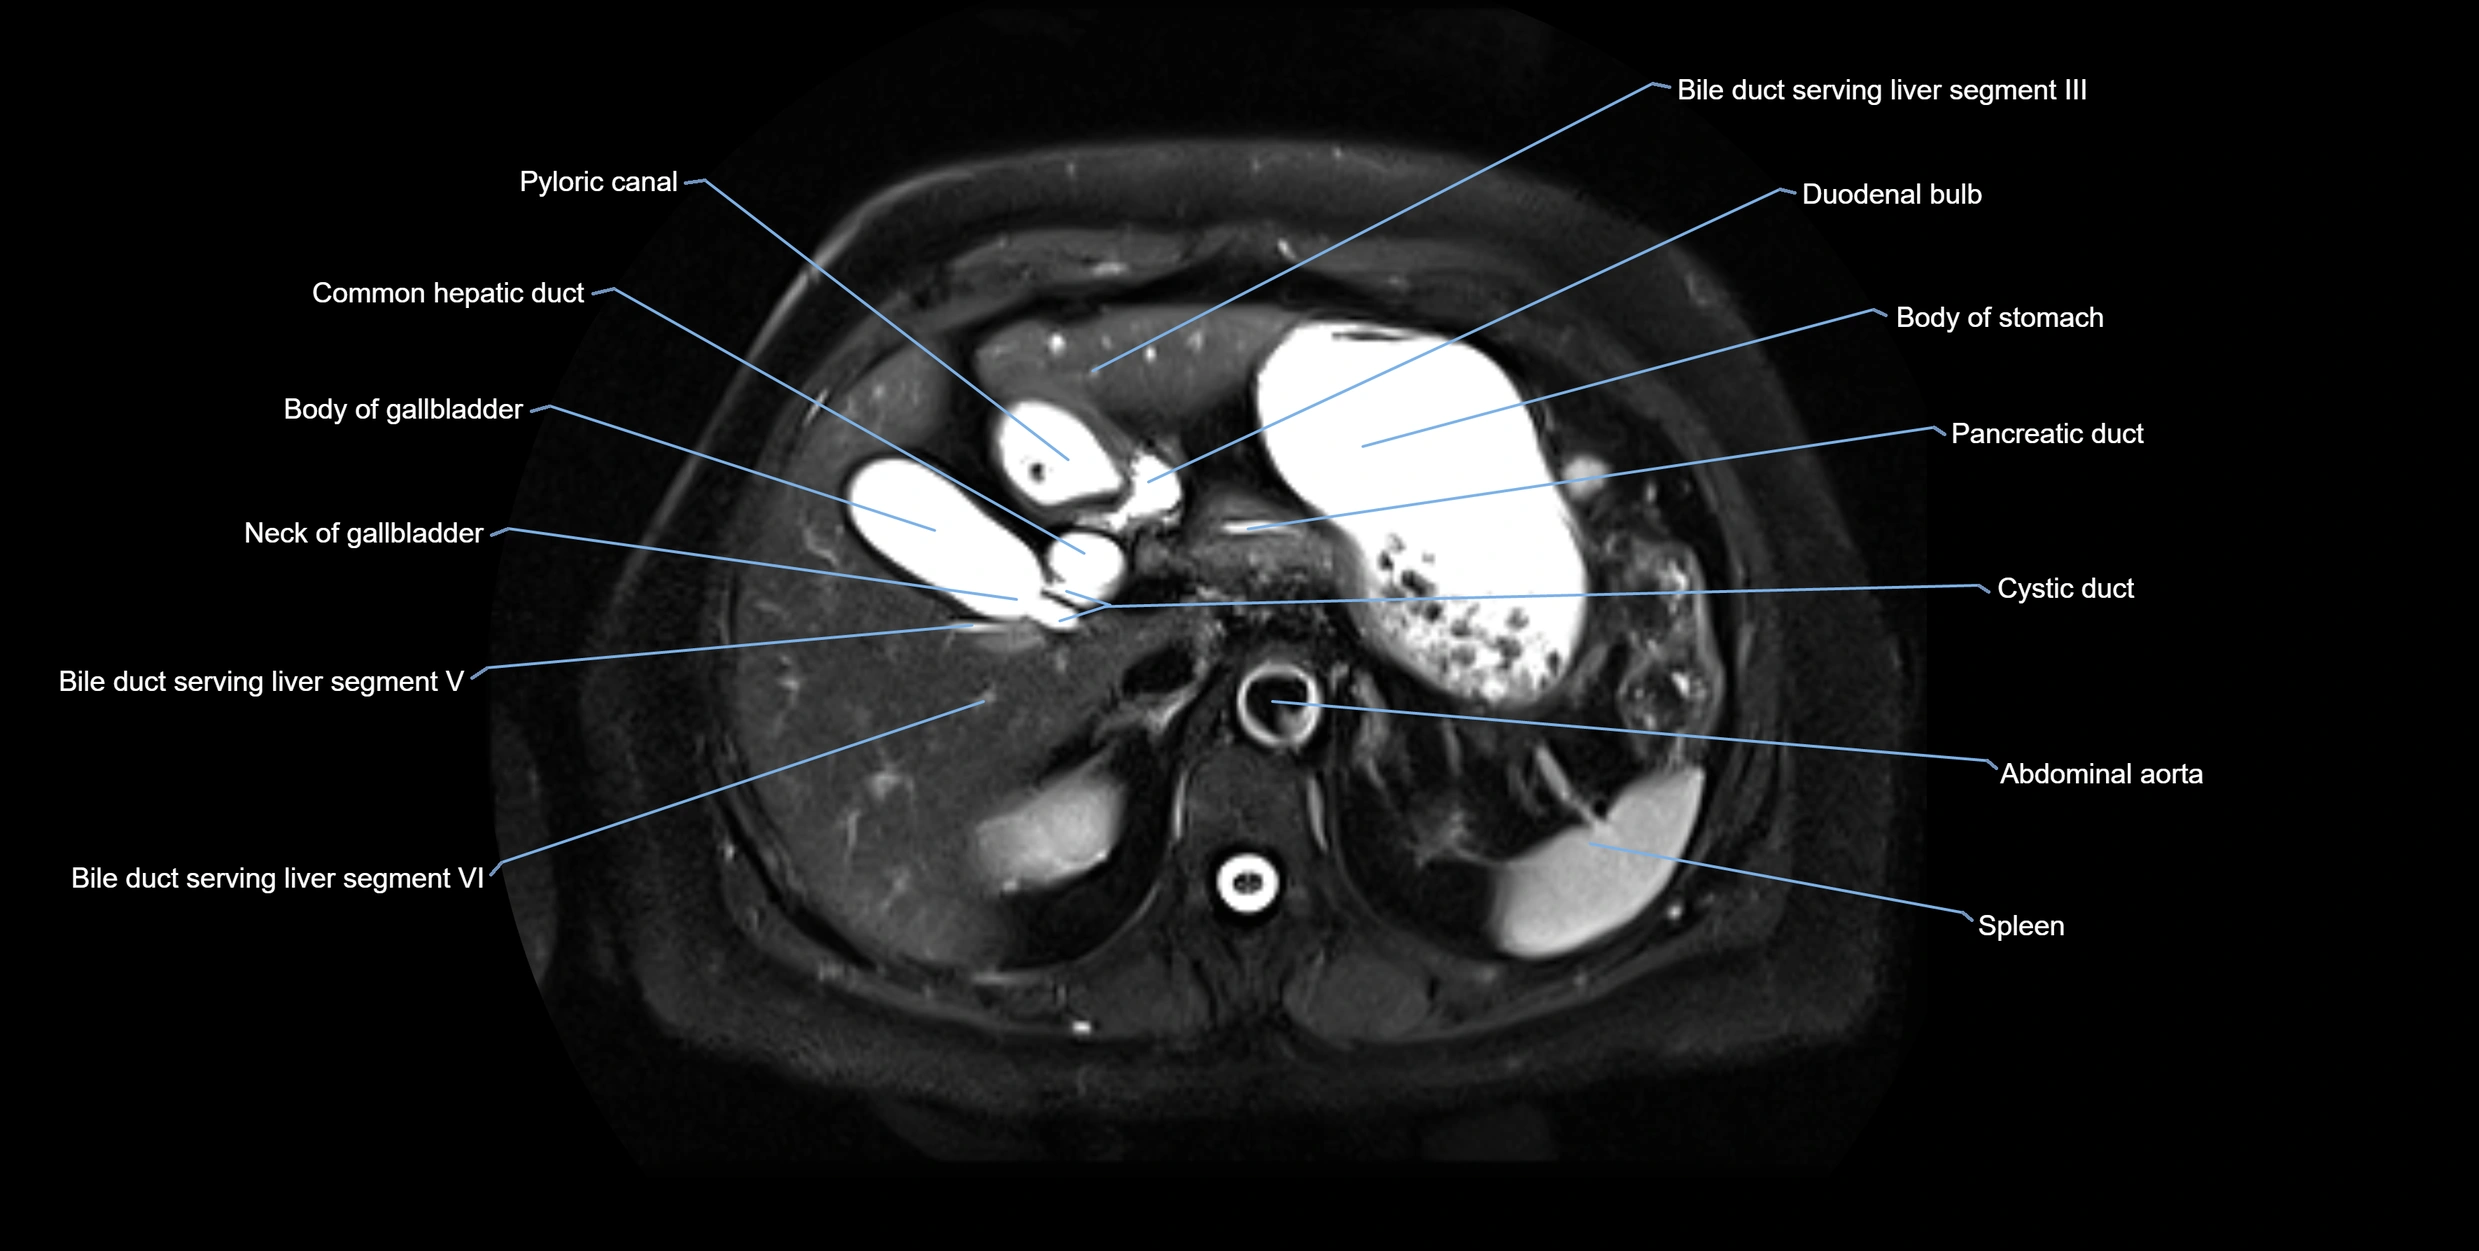

MRI image

image

Fullscreen Image